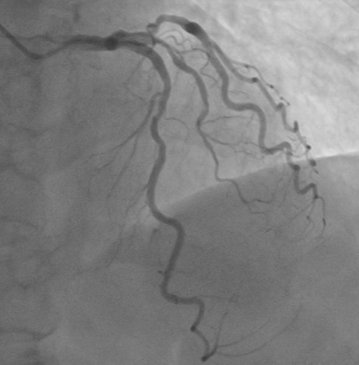

Right Coronary Angiography via right radial artery using 5 Fr TIG Optitorque demonstrated a tight lesion at mid part of Right Coronary Angiography (RCA) with heavy calcification. Left coronary angiography demonstrated non-significant stenosis at Left Anterior Descendent (LAD) and Left Circumflex (LCx) arteries. Therefore, the patient was planned to undergo PCI procedure via femoral access with IVUS guidance and preparation for rotablation.